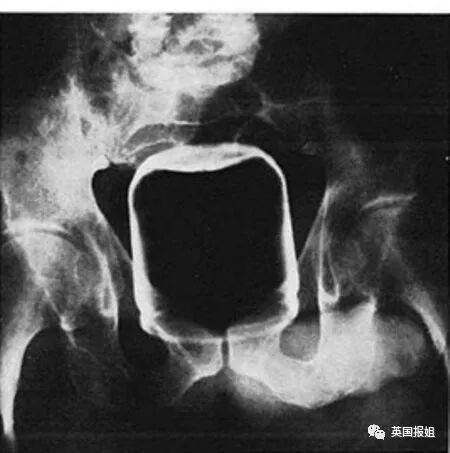

▷一个大啤酒杯

这位不愿意透露姓名的男士,坚称自己把啤酒杯塞进屁股里,是为了“减轻便秘。”